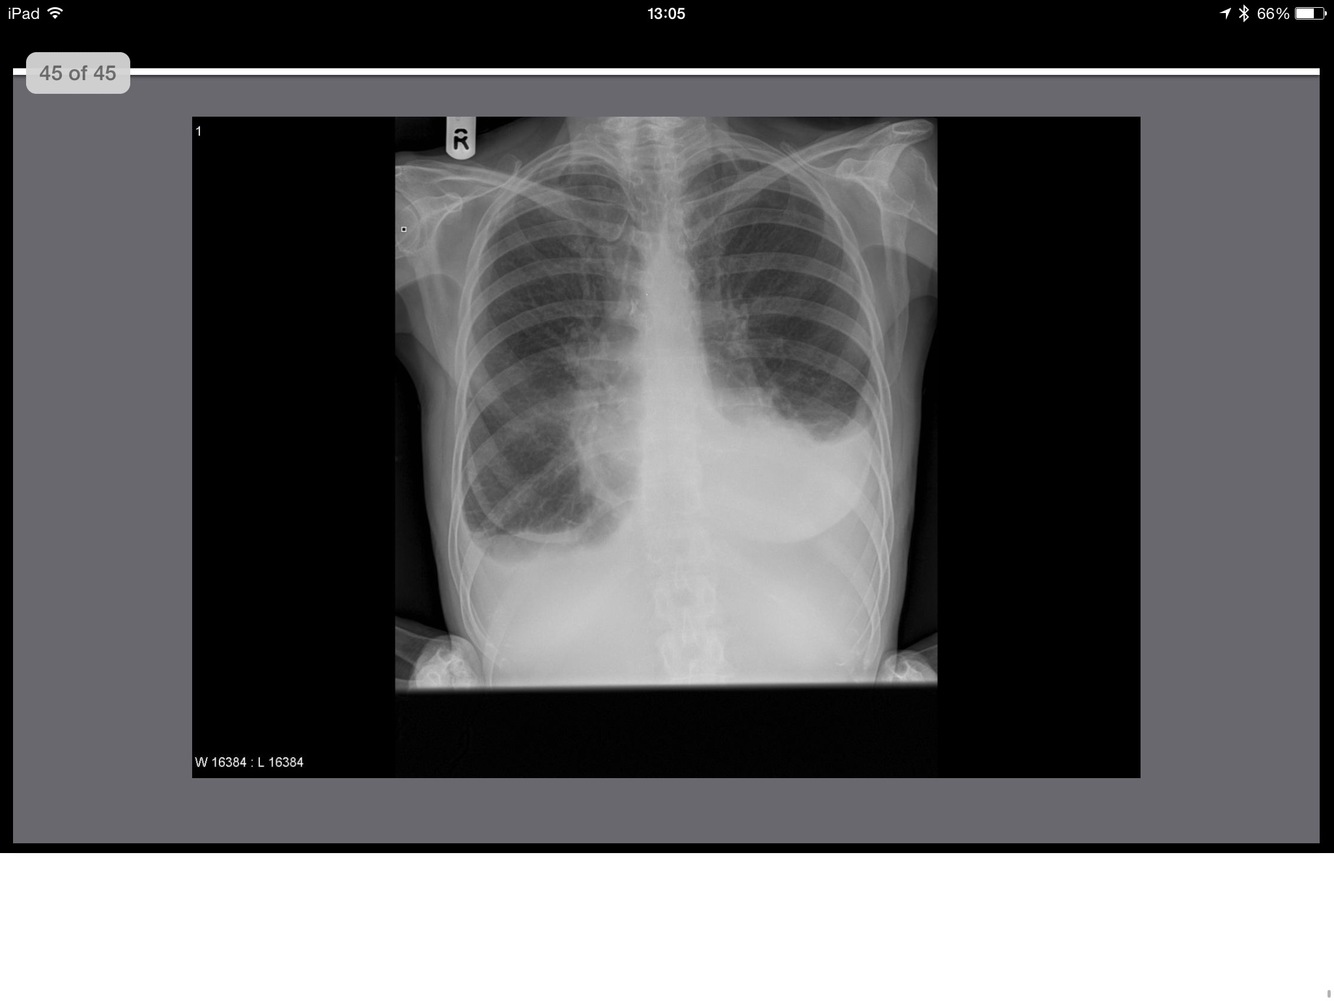

Point to them!

whatis the abnormality?